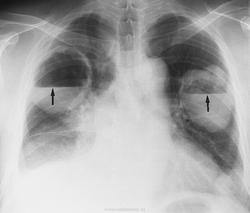

Множественные метастазы.